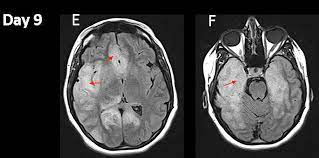

In children older than 3 months and in adults brain biopsy: Herpesviral encephalitis, or herpes simplex encephalitis (hse), is encephalitis due to herpes simplex virus. • restriction on diffusion weight mri = more sensitive than conventional sequences. Misra uk, hashmi aa, kalita j. Diagnostic uncertainty and empirical management in pcr negative encephalitis. It is a severe condition brain mri may show limbic encephalitis (55) or diffuse t2 and dwi hyperintensities in the white matter, associated with restricted diffusion (54). Herpes simplex encephalitis occurs as 2 distinct entities: Mri is the imaging of choice in suspected cases of viral encephalitis, although ct scanning may be used where mri facilities are not available. The patient had initially improved after medical treatment. Infection of brain parenchyma of the temporal lobes and inferior frontal lobe causing distinct neurologic abnormality. Dhawan a, kecskes z, jyoti r, kent al. Associated with hsv encephalitis (strong evidence). In addition, because of the involvement of the.

Herpes simplex virus (hsv) encephalitis hsv encephalitis (hsve) is the most common cause of infectious encephalitis (1); Initially clinical and brain mri findings were in favor of herpes simplex virus (hsv) encephalitis. The laboratory diagnosis of autoimmune encephalitis. Acute hsv encephalitis who had neuroimaging repeated within four weeks of the first scan. • occurs despite blood brain barrier with tight junctions.

The laboratory diagnosis of autoimmune encephalitis. The study analysed serially acquired magnetic resonance images (mri), of patients with acute hsv encephalitis who had neuroimaging repeated within four weeks of the first scan. Associated with hsv encephalitis (strong evidence). Its symptoms are fever, confusion, coma, and seizures. A case of granulomatous hsv encephalitis: Having said that, mri with contrast is considered the most sensitive imaging modality, and findings are present in over half of individuals 8. Severe infection, particularly untreated herpes simplex virus (hsv) encephalitis, can cause brain hemorrhagic necrosis. Herpes simplex encephalitis occurs as 2 distinct entities:

It is a severe condition brain mri may show limbic encephalitis (55) or diffuse t2 and dwi hyperintensities in the white matter, associated with restricted diffusion (54). Brain mri—increased t2 signal intensity in frontotemporal region → viral (hsv) encephalitis. Associated with hsv encephalitis (strong evidence). Provided cranial imaging has excluded any contraindications such as a space occupying lesion or severe cerebral oedema and brain shift, a csf. Having said that, mri with contrast is considered the most sensitive imaging modality, and findings are present in over half of individuals 8. In addition, because of the involvement of the. We performed volumetric measurements of the left and right temporal lobes and of cerebral oedema. Herpes simplex encephalitis occurs as 2 distinct entities: The study analysed serially acquired magnetic resonance images (mri), of patients with acute hsv encephalitis who had neuroimaging repeated within four weeks of the first scan. Pregnancy the most common cause of encephalitis in newborns is vaginal delivery from a mother who is infected with herpes simplex virus 2 (hsv 2). There is no particular age, sex, or seasonal predilection. Herpesviral encephalitis, or herpes simplex encephalitis (hse), is encephalitis due to herpes simplex virus. Severe infection, particularly untreated herpes simplex virus (hsv) encephalitis, can cause brain hemorrhagic necrosis.